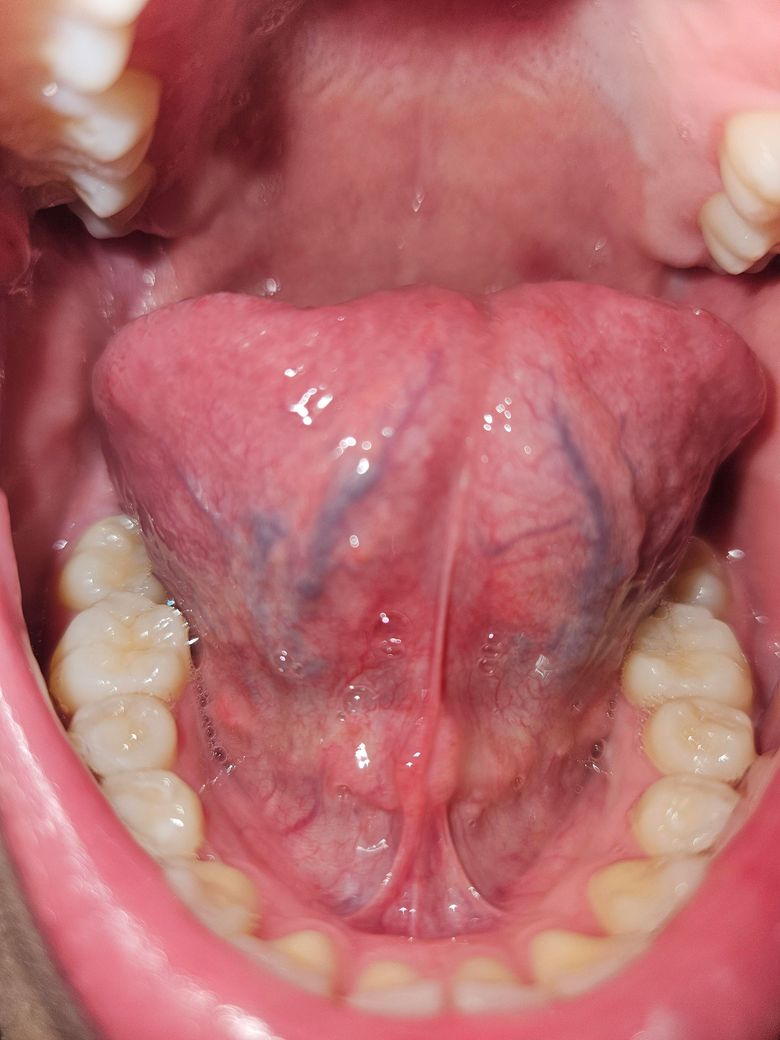

특히 혀는 하얀게 원래도 많았지만 평소보다 많아졌고 빨간 반점 같은 것과 식도 근처에 종기 같은게 보입니다... 사진에는 안보이지만 입 천장에는 만져도 안아픈 혹이 한 두개 정도 만져지고 혀 뒷쪽은 더 큰 종기 같은게 육안으로 더 보입니다.

• 1번 째 사진